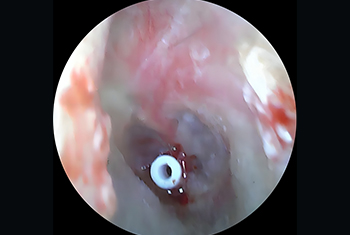

Comprehensive care for ear infections and hearing loss, including Tympanoplasty, Mastoidectomy, Ossiculoplasty and Stapedotomy/Stapedectomy for improved hearing outcomes.